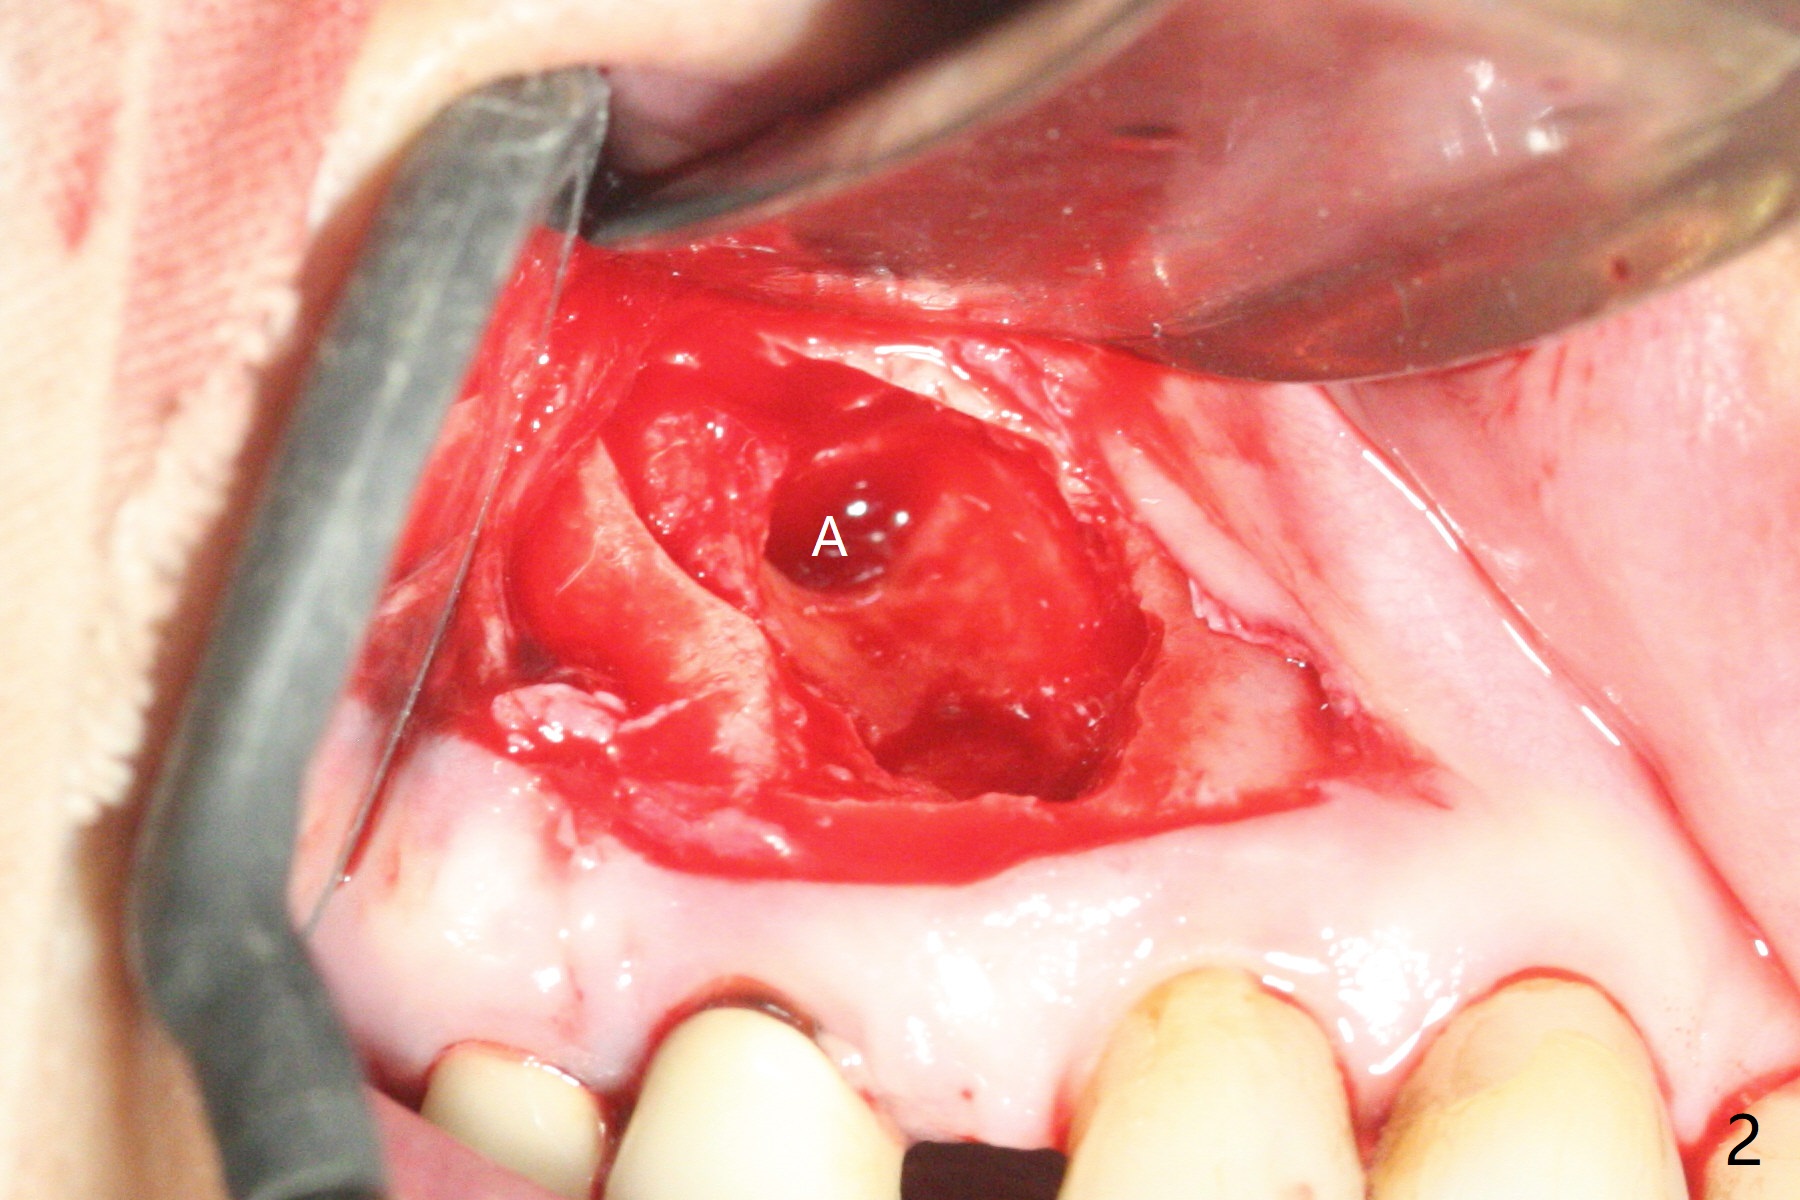

After incision and flap elevation, the crown of the impacted canine is more superficial. With removal of the buccal cortical plate and multiple sectioning of the crown, the latter is removed (Fig.1 *). Further removal of the buccal plate (P) and purchase points, the root (R) is extracted easier. In fact the apex of the root is the deepest (Fig.2). With the guide (Fig.3 G) and 2.2 mm drills, the osteotomy is established. It is pretty shallow. A 3x18 mm drill is used to deepen the osteotomy free hand (mistake: too palatal). When a 3.8x18 mm UF implant is being placed, it cannot be placed deep with the guide. When the latter is removed, the implant seems to be placed too deep and too buccal with <10 Ncm (Fig.4). A 4.5x7(5) mm abutment is placed mainly to correct the trajectory of the implant to certain degree. Placement of the implant at #3 is quite smooth (Fig.5) in spite of severe bone loss and abundant granulation tissue at #3 and 5. The implant at #5 does achieve 2 pointed fixation (Fig.4,6 arrowheads). The most coronal portion of the canine crown is left behind (Fig.6 C).